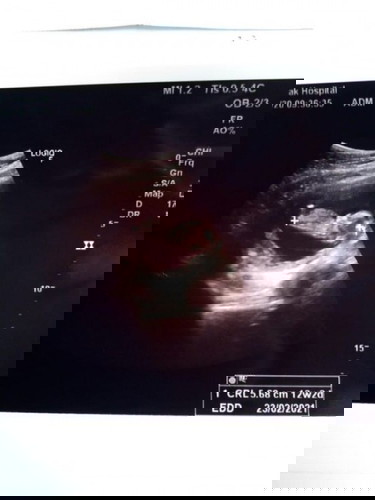

ตัวเล็กไปไหม12week3วันแล้ว หมอบอกน้องยาว 5.68เซน

12w2d ค่ะ ไม่ใช่3w3d☺